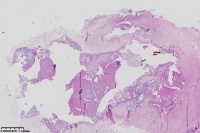

臀部包块,请教老师们

女

55岁

臀部包块

异物肉芽肿,结合相关病史

考虑: 异物性肉芽肿。